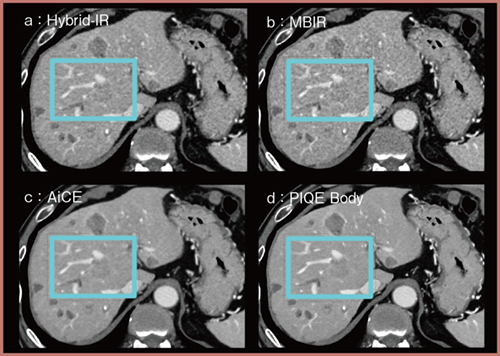

代表的な症例を提示する。図3は肝ダイナミックCT門脈相の画像であるが,PIQE Body(d)ではAiCE(c)と遜色のないノイズ低減が得られている。また,空間分解能も高く,一部を拡大すると(図4),PIQE Body(d)では血管の鮮鋭度が最も高く描出されており,腫瘍が血管に浸潤する様子も良好にとらえられている。

図3 肝ダイナミックCT門脈相における画像比較

図4 図3の一部を拡大した画像